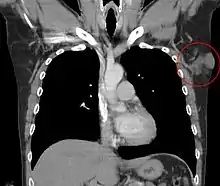

Metastases to regional lymph nodes are extremely rare.[34] Distant hematogenous metastases are even rarer and are most likely in patients who have had multiple local recurrences after inadequate surgical resection.[35] Repeatedly recurring tumors have an increased risk for transformation into a more malignant form (DFSP-FS). The lungs are most frequently affected, but metastases to the brain,[36] bone,[37] and other soft tissues are reported.